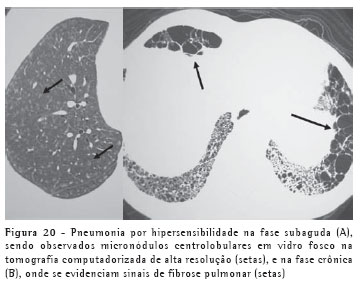

A pneumonia por hipersensibilidade pode ter apresentações aguda, subaguda e crônica. Os achados de imagem variam de opacidades e consolidações, na forma aguda, a micronódulos centrolobulares em vidro fosco (subaguda) e sinais de fibrose pulmonar na fase crônica (Figura 20).